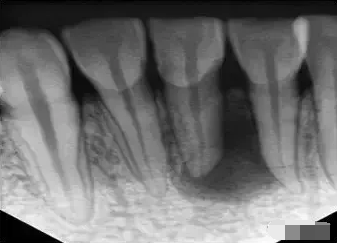

1、術(shù)前拍攝X線片

在根管治療過程中,在根管治療術(shù)前拍X線片,以幫助診斷,了解髓室的位置和根管數(shù)目及形態(tài),測量根管工作長度及日后隨訪和評價療效提供對比的依據(jù)。

應(yīng)用平行投照X線方法、根管長度測量儀確定根管度,最好插針拍X片。

封閉整個根管系統(tǒng)、堵塞主根管和側(cè)副根管出口、防止微生物和液體的滲漏。無論是側(cè)方加壓法還是垂直加壓法,應(yīng)做到根管充填致密,根管充填后X線片上無根管腔隙,也不能超出根尖孔。

X線片顯示根管充填完好,行暫時或永久牙體修復(fù),帶上牙冠,保護患牙。至此根管治療才可算完成,同時根管治療后還需復(fù)診,一般周期可為3個月、半年、1年、2年或更長。